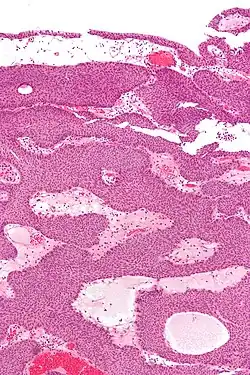

Histopathology representing an inverted papilloma of the urinary bladder that was cystoscopically resected. Hematoxylin and eosion stain.